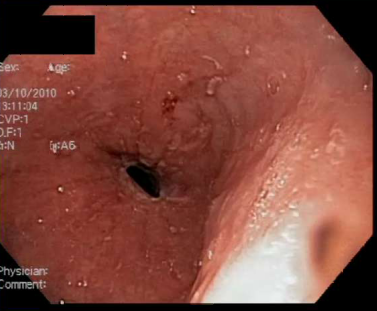

This is eosinophilic esophagitis, note the eosinophilic microabscesses on the esophageal wall and concentric rings. This is diagnosed by biopsy w/15-20 Eos per high power field.

How do patients with EoE typically present first and how do you first manage them?

1st: intermittent dysphagia. Treat w/PPI, then if that doesn’t work you treat with topical steroids.